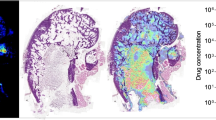

Detection of methadone and metabolite in postmortem forensic human bone

A clavicular bone of a 37-year-old male who died of an overdose of methadone was sectioned cross-sectional and imaged as described. Blood concentrations of methadone and EDDP were respectively 3727.4 ng/mL and 32.9 ng/mL as described in Vandenbosch et al. [25]. When looking at the distribution image of methadone, the bone marrow could be distinguished from the surrounding bone (see Fig. 4). In addition, the bone tissue could clearly be distinguished from the surrounding matrix. Similar observations were made for EDDP (see Fig. 4).

Distribution images of methadone and EDDP in a human clavicle from someone who overdosed on methadone. a Cross section of the clavicle with the region of interest (ROI) in blue. b MALDI-MSI distribution image of methadone (m/z 310.21). c MALDI-MSI distribution image of EDDP (m/z 278.18). The distribution images are total ion current (TIC)-normalized. Scale bar shows relative intensities

In positive ion mode, different matrices allowed for the detection of different molecules from the bone and bone marrow, although some m/z values were represented in multiple matrices (see Fig. 5). For DAN, DHA, and norharmane, it was not possible to obtain specific m/z values from bone, although for norharmane some m/z values showed higher intensities in bone tissue compared with the bone marrow and surrounding tissue. For CHCA and DHB, it was possible to obtain m/z values specific for bone and bone marrow. In addition, CHCA and DHB had the highest number of m/z values specific for bone or bone marrow (see ESM Table S2). DAN and norharmane resulted in a high number of specific m/z values for bone marrow compared with DHA. For CHCA, the specific m/z values were roughly half divided between bone and bone marrow, while for DHB, the majority of the specific m/z values were obtained from bone (see ESM Table S2). DHB has relatively low signal intensities (TIC-normalized) and signal-to-noise (S/N) ratios (see ESM Table S2 and mass spectra in ESM Fig. S4) for bone as well as bone marrow compared with the base peak, while CHCA has low signal intensities and S/N ratios for bone in contrast to data collected from bone marrow. DAN provided the highest S/N ratios for signals derived from bone marrow, but in the positive ion mode, this matrix showed significant interference with the tissue-related peaks. DHB and norharmane show some interferences, and for CHCA and DHA, the interference is low (ESM Fig. S4).

Overlay images of selected m/z values for CHCA, DHA, DAN, DHB, and norharmane in positive ion mode measured with MALDI-MSI of mouse hind legs for the untargeted detection of lipids. The m/z values were selected to show the similarities and differences between the matrices in terms of desorption and ionization efficiency. a Optical scan of the section with the measured area indicated with a black line. Overlay images of the distributions of selected m/z values in the range 200–500 (b), 500–600 (c), and 700–800 (d). The distribution images are total ion current (TIC)-normalized and the intensity scale shows the maximum relative intensity of the specific m/z value (for tentative identifications of the selected m/z values, see ESM Table S3)

In the MALDI-MSI experiments, methadone (m/z 310.21) and EDDP (m/z 278.18) were distinguishable from background signals in the bone marrow of the rat and human bone (see Figs. 3 and 4). Confirmatory MS/MS experiments were not performed due to the low intensities of our analytes, but high mass accuracy of the oToF system strongly corroborates our so far tentative assignment. Internal calibration of the instrument was performed daily in the mass range 50–650 Da (< 1 ppm) using red phosphorus. Afterwards, the mass accuracy was checked with quality control samples in the form of calibration series spiked on blank bone sections. Aside to that, the untreated and dosed bones were analyzed in the same experimental run to ensure a consistent mass accuracy.